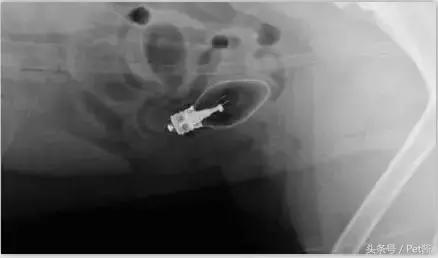

而只有拍片的时候你才知道狗狗的肚子里到底有什么东西,所以如果狗狗吃了什么奇怪的东西导致拉肚子,宠物医生肯定第一件事就是让你去拍片。

这天回家她发现家里的二哈突然开始拉肚子,连断食都没有用。然后她发现鞋柜上的臭袜子少了一只,在加上狗狗在成长期现在很喜欢咬东西磨牙,狗主人马上反应过来狗狗是因为将袜子吃掉后生病拉肚子。